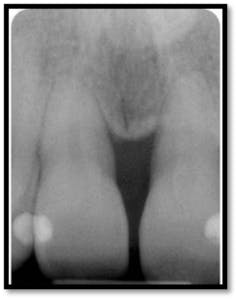

Probing depths posterior and anterior teeth 3-4mm

Note the bone fill on the vertical defects of #8-9 and 18 and 19